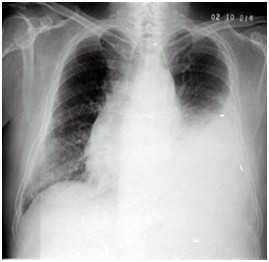

02卷-5.女性,55歲,胸悶、氣短5天,加重1天。診斷(本題滿分2.00分)

A.右上肺炎

B.左側(cè)胸腔積液

C.左下肺不張

D.左肺癌

本題答案:B

題目解析:

【該題針對(duì)“ X線-胸腔積液 ”知識(shí)點(diǎn)進(jìn)行考核】